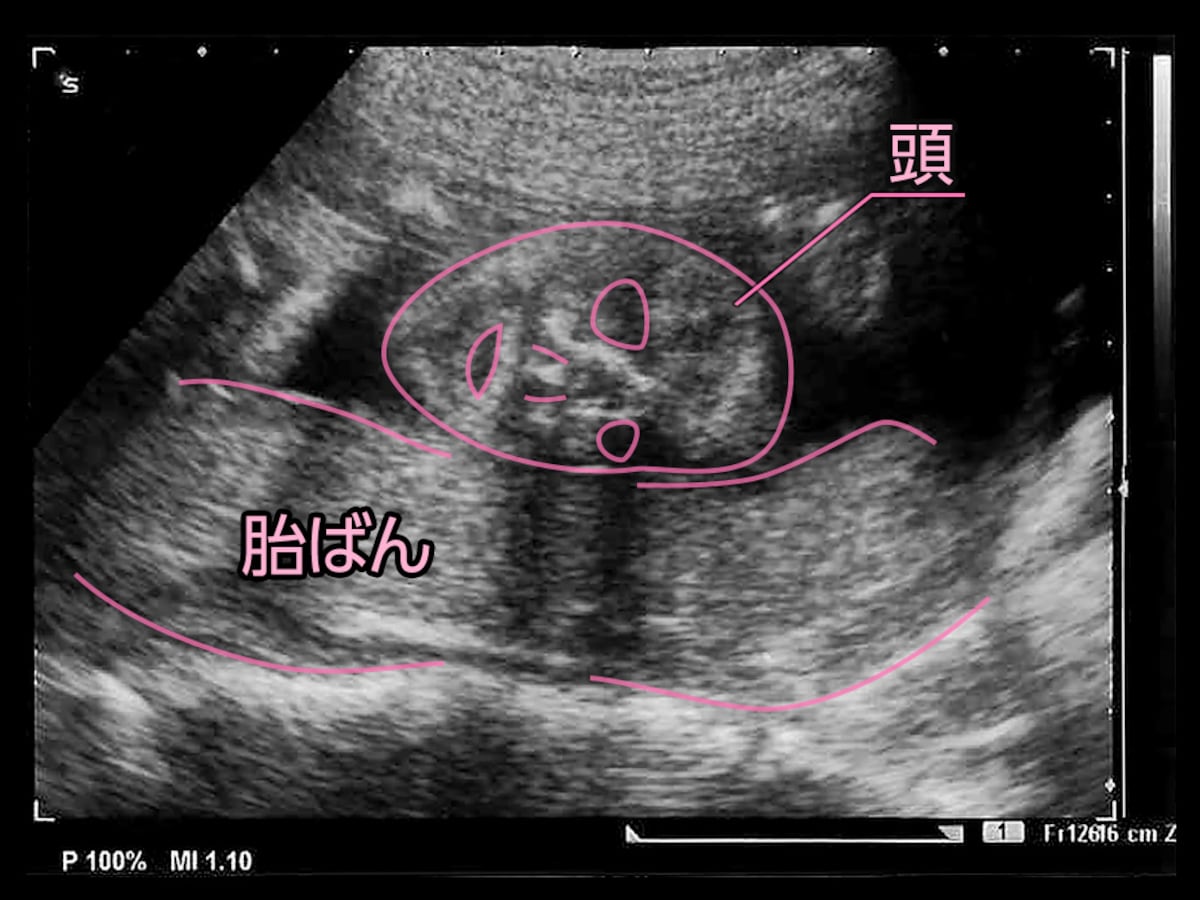

エコー写真を妊娠の経過別に紹介 見方や性別の見分け方

エコー写真を妊娠の経過別に紹介 見方や性別の見分け方

医療監修 エコー写真を妊娠の経過別に紹介 写真の見方や性別の見分け方 ママリ

妊娠23週3日 23w3d の超音波 エコー 写真

エコー写真を妊娠の経過別に紹介 見方や性別の見分け方

エコー写真を妊娠の経過別に紹介 見方や性別の見分け方

エコー写真を妊娠の経過別に紹介 見方や性別の見分け方